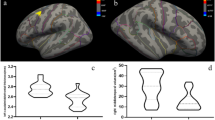

These different brain structures between groups including left frontal pole volume as well as right bankssts and inferior parietal cortical thickness were regarded as features for machine learning classification. Among seven predictive models, SVM was identified as the optimal algorithm for violence in SCZ with a balanced accuracy of 0.8231 and an AUC of 0.8410 (Table 3 and Fig. 1).

The main findings in the present study were that after controlling for the whole-brain volume and age, the SCZ individuals with a history of violence showed reductions in several brain regions involved in emotion and cognition processing, including left frontal pole volume as well as right bankssts and inferior parietal cortical thickness, compared to those without a history of violence. Subsequently, these different brain structures between groups were used to develop the prediction models for violence among SCZ patients using machine learning method. Ultimately, seven predictive models were established. Through comparing with each other, the SVM had the best performance with a balanced accuracy of 0.8231 and an AUC of 0.841.

In our study, we found SVM was appropriate to structural MRI data and had better predictive performance in differentiating violent from non-violent patients with SCZ than other six machine learning algorithms, with its balanced accuracy and AUC reaching 0.8231 and 0.841, respectively, similar to previous findings that SVM has promising results in neuroimaging [36]. The possible reason is that SVM belongs to one of the machine learning algorithms which can process high-dimensional data and capture nonlinear variable relations. Considering that neuroimaging data are likely to be nonlinear, SVM is able to achieve better performance than other algorithms [37]. To date, studies predicting risk of violence in SCZ patients using neuro-imaging data are sparse. The only research employed multimodal MRI and SVM to identify SCZ patients at high risk of violence. The model based on the single modality of gray matter volume showed an accuracy of 77.33% and an AUC of 0.80 [22]. The possible reason for different predictive power is that our model included more characteristics of cortical morphology, namely cortical surface area, gray matter volume and cortical thickness, to improve the power of recognizing the patients with greater risks of violence. Besides, there have been a few studies which combined machine learning algorithms and demographic and clinical data to differentiate patients with violence from those without violence, but the performance of prediction models was unsatisfactory [11,12,13]. In this study, the prediction model integrating structural MRI characteristics demonstrated good performance. Above evidence suggests that due to high anatomical resolution of cortical volume, area and thickness, structural MRI features can be suggested to be biologically-based predictive markers.